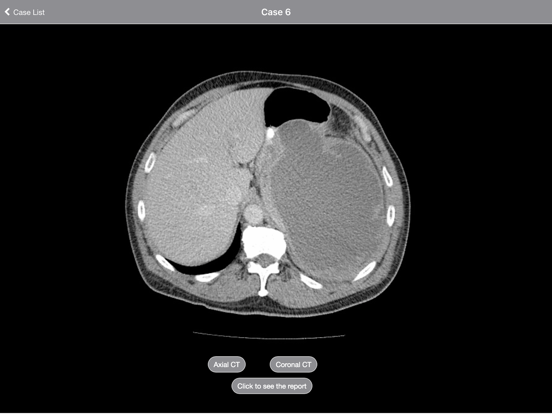

Each case is presented as a complete CT or MRI scan that you can scroll through as if at a PACS workstation. Multiple sequences in multiple planes are presented for every case. Report, short discussions, and pathology/clinical followup are presented for each case.

The interface incorporates image zoom and pan. In addition, both portrait and landscape orientations are supported.